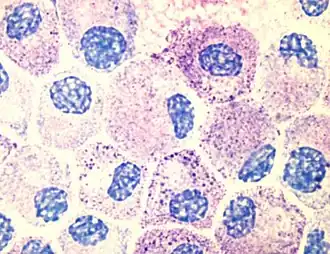

![]() Imagen tomada con un microscopio óptico, en la que se observan mastocitos teñidos con azul de toluidina. | ||

Presentan un núcleo central de tamaño medio, con la cromatina desespiralizada. En microscopía óptica solo se pueden distinguir en el citoplasma unos gránulos de gran tamaño, rodeados de membrana y visibles con la técnica del PAS+. Estos gránulos tienen la propiedad de ser metacromáticos, es decir, tienen la capacidad de cambiar el color del colorante con el que son teñidos. Por ejemplo, al utilizar la tinción azul de toluidina, con el cual se puede apreciar que los gránulos se tiñen de púrpura . Lo mismo pasa con colorantes como el Giemsa y el azul de metileno.

Mediante microscopía electrónica puede observarse en el citoplasma unos pequeños vestigios de aparato de Golgi y de retículo endoplasmático rugoso (RER), no muy desarrollados. Sin embargo, esto no impide que estas células lleven a cabo una gran labor de síntesis. No obstante, es muy difícil diferenciar los gránulos de las vesículas de RER y Golgi. El contenido de los gránulos es muy denso, llegando en ocasiones a formar agregados o incluso una especie de laminillas. Su citoplasma es acidófilo con abundantes gránulos metacromáticos al azul de toluidina.